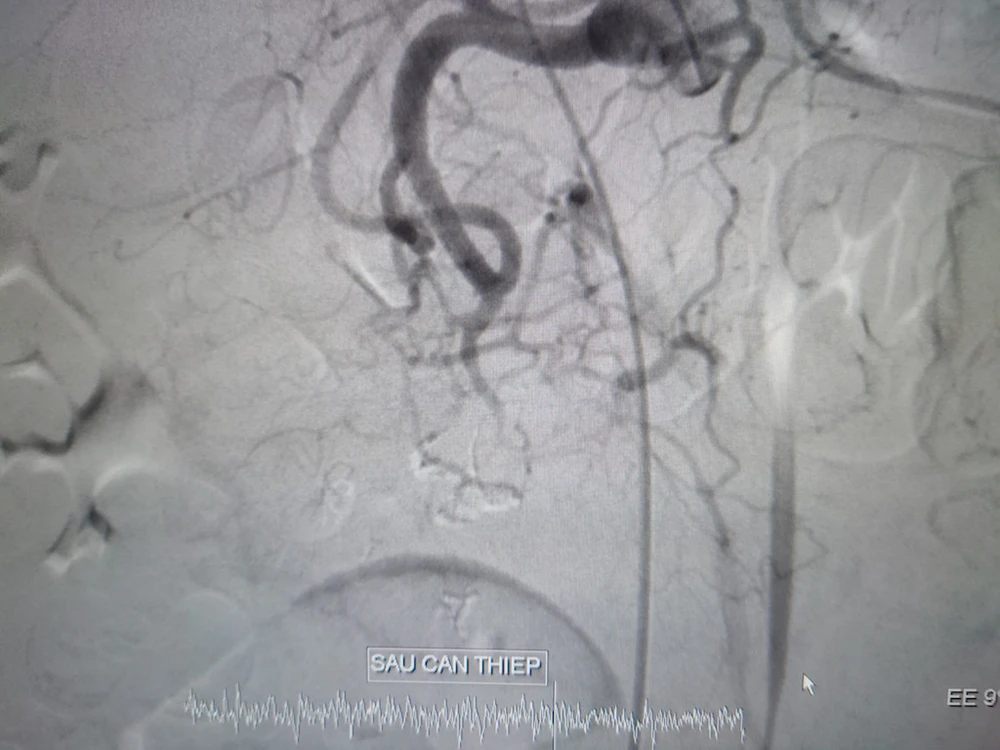

Động mạch vị tá tràng trước và khi can thiệp. Ảnh: BVCC 1 Động mạch vị tá tràng trước và khi can thiệp. Ảnh: BVCC 2

Động mạch vị tá tràng trước và khi can thiệp. Ảnh: BVCC

Kết quả chụp và can thiệp nội mạch xác định bệnh nhân bị xuất huyết nội do vỡ phình động mạch vị tá tràng, nhiều ổ thoát mạch từ nhánh của động mạch vị tá tràng cấp máu vùng tá tràng đoạn DIII, tắc hoàn toàn nhánh thoát mạch.

Ê kíp y bác sĩ đã tiến hành can thiệp tắc mạch bằng hỗn hợp keo trong 40 phút. Hiện bệnh nhân tỉnh, sinh tồn ổn, niêm hồng, bụng mềm, không sốt, tình trạng chung ổn, đang được theo dõi và điều trị tiếp tại Khoa Ngoại lồng ngực - mạch máu.